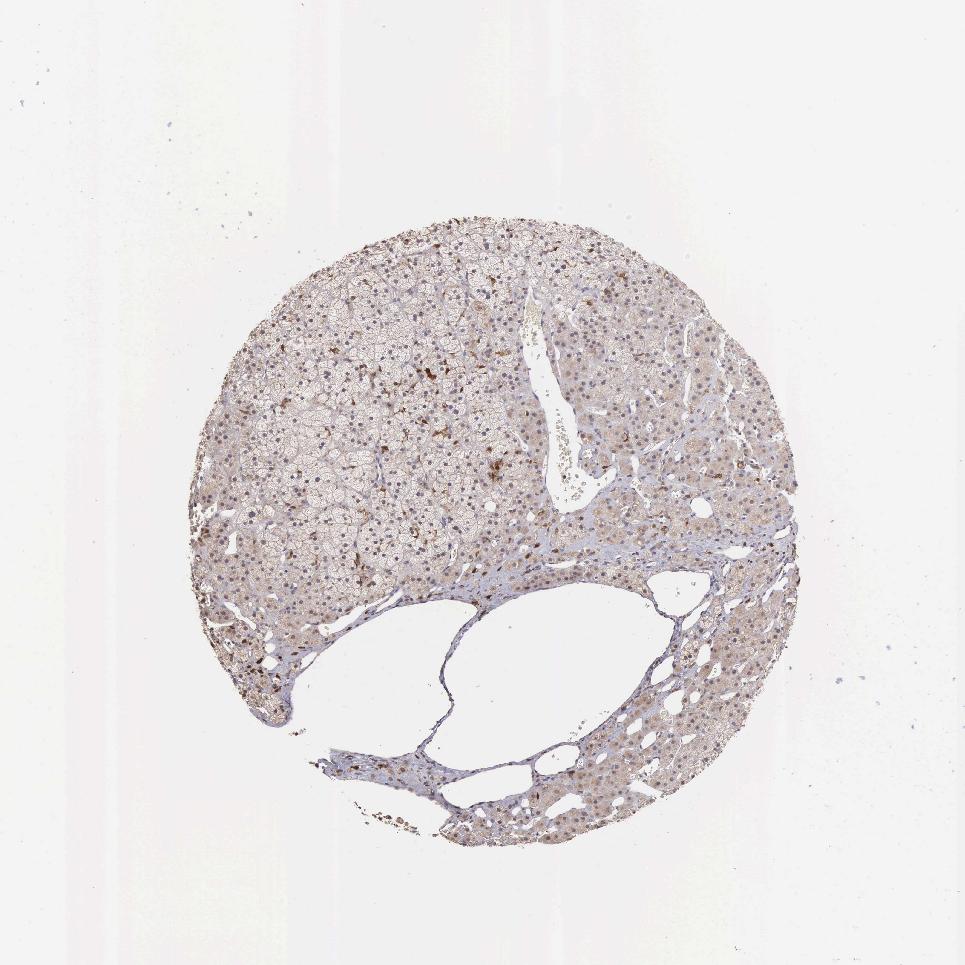

ADRENAL GLAND - Antibody stainingi

Antibody staining in the annotated cell types in the current human tissue is reported as not detected, low, medium, or high, based on conventional immunohistochemistry profiling in selected tissues. This score is based on the combination of the staining intensity and fraction of stained cells.

Each image is clickable and will lead to virtual microscopy that enables deeper exploration of all samples and also displays staining intensity scores, fraction scores and subcellular localization as well as patient and tissue information for each sample.

Antibody HPA000614Antibody CAB009459

Glandular cells Not detectedNot detected